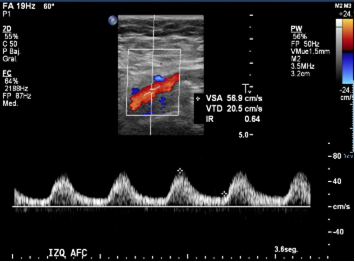

Se observan curvas monofásicas de baja resistencia con disminución de su velocidad en todas las ramas arteriales de ambas extremidades inferiores, tipo tardus parvus. Se evalúan arterias iliacas comunes y externas observando similares características.

Se observan curvas monofásicas de baja resistencia con pérdida de componente reverso diastólico y disminución de la velocidad sistólica en todo el árbol arterial de ambas extremidades inferiores. En la aorta abdominal distal, a 3 cm de la bifurcación, se observa un segmento oclusivo de la aorta con contenido ecogénico calcificado, sin flujo a este nivel. Previo a la oclusión se observa curva pre oclusiva monofásica de baja velocidad. Se observa flujo colateral paralelo a la oclusión que reconstituye el flujo en el origen de las arterias iliacas comunes, observándose flujos monofásicos hacia distal con reducción en aproximadamente un 60%